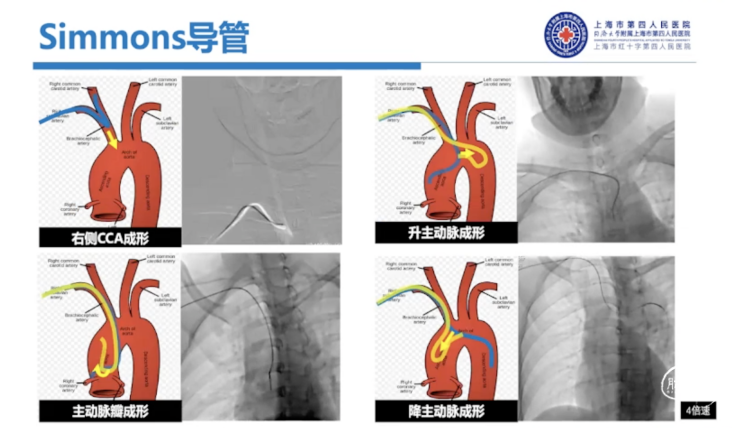

不同Sim导管尺寸对弓上超选也是有影响的,通常在右侧颈总动脉成型、升主动脉成型时更常用Sim I,Sim I头端较短,非常容易通过主动脉弓进入降主动脉。

主动脉瓣成型一般使用较少,但是如果弓型比较特殊,我们使用Sim I导管完成主动脉瓣成型还是非常有效的,对于降主动脉成型以及左侧经桡成形,我们一般会选择Sim II。